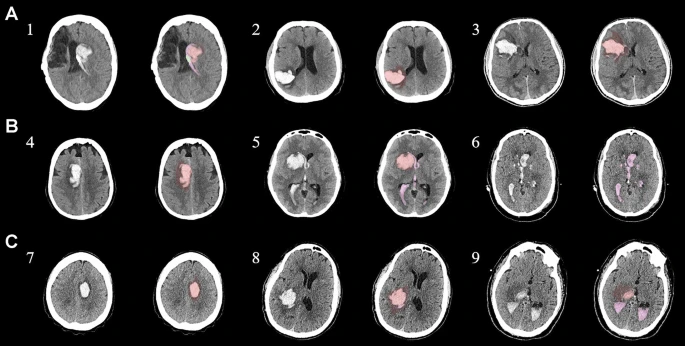

具有臨床特征的探索性成像體積模型分析

ABC/2模型1和模型2分割方法通過ICH和IVH體積的線性回歸顯示出良好的相關性(圖3a、b)。與模型2分割體積方法(例如,每個CT15-20分鐘)相比,模型1ABC/2派生的半定量方法和改進的Graeb IVH方法完成時間較短(例如,2-5分鐘)。有趣的是,NIHSS評分與IVH體積M2方法的比較顯示出線性相關性(R 2 ?= 0.7217),并且當IVH小于20mL或大于20mL時,NIHSS評分似乎出現(xiàn)聚類(圖3c)。PHE分析顯示MSC注射劑量和PHE體積之間存在輕微的負相關關系。

a,通過模型1ABC/2派生方法與vol模型 2(分割)進行的神經(jīng)影像ICH vol的線性回歸。b、IVH通過模型1和定量分割模型2方法對Graeb進行了修改。c,出血量和NIHSS評分與IVH量通過分割進行比較。